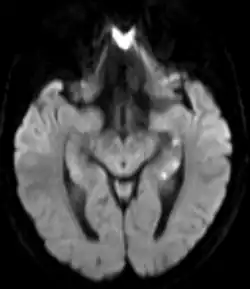

Areas of hypoperfusion, seen above in the left sided hippocampus (seen as white punctate lesions on diffusion weighted MRI) are a characteristic finding in Transient Global Amnesia

There is no universally accepted diagnostic criteria for TGA, however proposed diagnostic criteria include: the absence of seizures, the absence of a head injury, symptoms that resolve within 24 hours, and the dysfunction or impairment being limited to amnesia (both retrograde and anterograde).[4] TGA is a clinical diagnosis and brain imaging or other testing is not required for the diagnosis.[4] However, brain imaging is often obtained to rule out other serious causes of sudden amnesia, including a stroke. Brain imaging is usually normal during and immediately after an episode of TGA. However delayed diffusion weighted MRI (obtained 12–48 hours after the episode) can sometimes show punctate lesions in the hippocampus (one of the areas of the brain responsible for memory) or adjacent areas of the brain. These lesions are transient; often persisting for several days after the episode.[4]

Functional MRI may show bitemporal hypoperfusion during an episode of TGA. Other areas affected include the hippocampus, parahippocampal gyrus, and amygdala.[4]